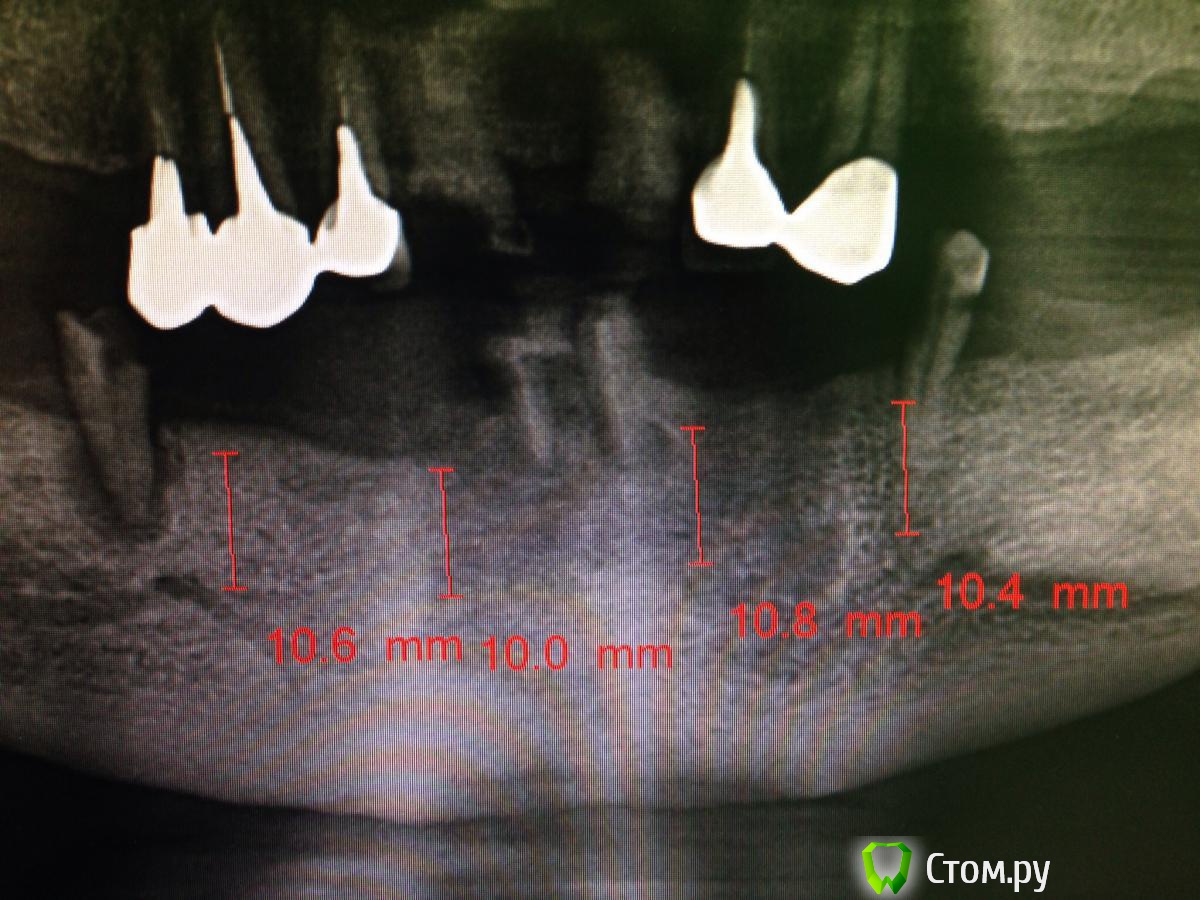

MaxDok Опубликовано 17 февраля, 2014 Поделиться Опубликовано 17 февраля, 2014 Благоприятная форма нижней челюсти для все на 4-х . А что у пациента сверху? Ссылка на комментарий

diesel87 Опубликовано 17 февраля, 2014 Автор Поделиться Опубликовано 17 февраля, 2014 еще забыл добавить, позиционирование имплантатов в уровне кости по горизонту должно быть более менее одинаковое, т.е русским языком говоря -- участок кости во фронте, лучше выравнить, но без фанатизма По поводу горизонтальной позиции и срезания не ровного гребня, что думаете по такой постановке Ссылка на комментарий

diesel87 Опубликовано 21 февраля, 2014 Автор Поделиться Опубликовано 21 февраля, 2014 В продолжение своей темы покажу что получилось 3 Ссылка на комментарий

doca Опубликовано 24 февраля, 2014 Поделиться Опубликовано 24 февраля, 2014 В продолжение своей темы покажу что получилосьPicsArt_1392992232297.jpgс таким положением имплантов -несъемнуй мост самое то 1 Ссылка на комментарий